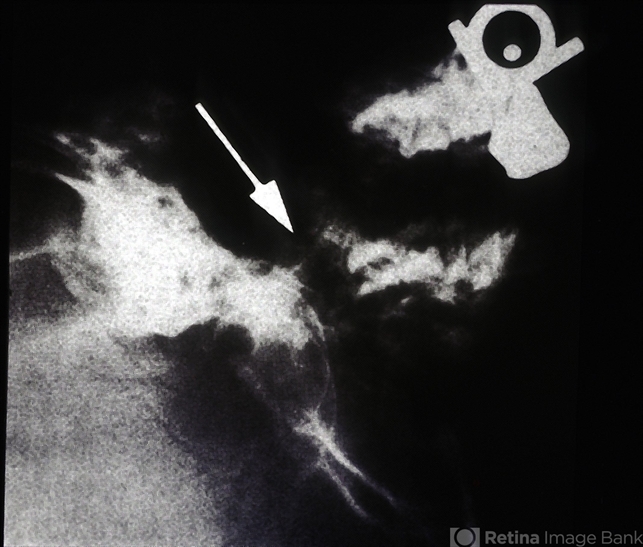

- optic nerve coloboma, Morning Glory Syndrome, encephalocele

- Morning glory with associated encephalocele protruding into nasopharynx.